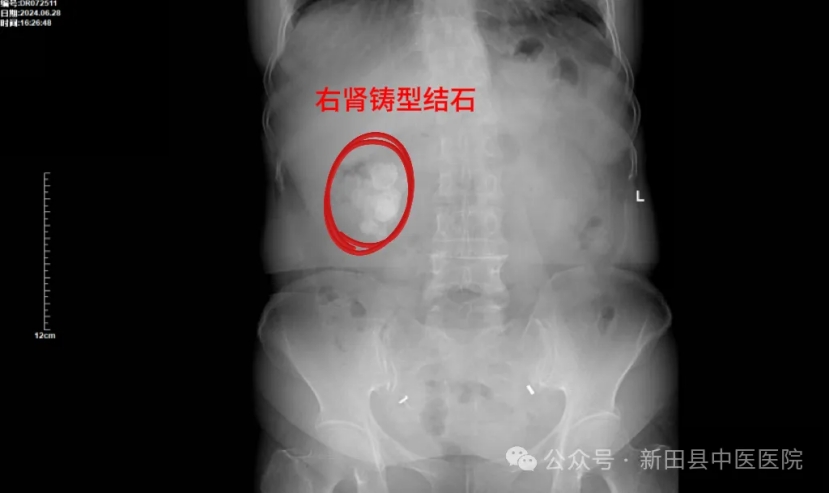

前段时间,55岁的陈女士在体检时,被查出右肾多发结石,且结石形似“鹿角”,属于典型的“铸型结石”。 真是“不查不知道,一查吓一跳!”

带着这些疑问,陈女士慕名到新田县中医医院找泌尿外科邓勇军主任求诊。邓勇军详细询问陈女士病史并进行了仔细体查,结合其检查报告“右肾多发结石,其中最大结石约40x27mm”,建议陈女士住院行手术治疗,并告诉她,肾脏巨大铸型结石是比较严重的,继续发展会导致肾脏积水,肾功能不全。

▲术前DR